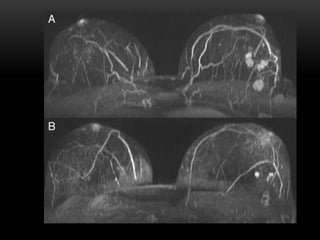

RESONANCIA MAGNETICA

EN MAMA

• La RM es una técnica con elevada

sensibilidad pero con una especificidad

limitada en el diagnóstico del cáncer

invasor de mama.

• Numerosos estudios avalan su utilidad en

el manejo de la patología mamaria,

especialmente en la estadificación pre-

quirúrgica del cáncer de mama.

INDICACIONES DE RM EN MAMA

1. Valoración de posible multicentricidad en la misma mama o en la contralateral

2. Determinar extensión preoperatoria de un tumor conocido.

3. Monitorización de la quimioterapia neoadyuvante.

4. Búsqueda de tumor primario con MX axilar

5. Estudio de posible enfermedad residual tras cirugía conservadora o

tumorectomía.

6. Valoración de pacientes con implantes mamarios.

7. Caracterización de lesiones no diagnosticadas con otras técnicas de imagen.

8. Estudio de posibles recurrencias del cáncer de mama.

9. Marcaje prequirúrgico mediante RM de mama.

10. Pacientes con alto riesgo individual de Ca de mama.

• La RMes una técnica con elevada sensibilidad pero con una especificidad limitada en el diagnóstico del cáncer invasor de mama. • Numerosos estudios avalan su utilidad en el manejo de la patología mamaria, especialmente en la estadificación pre- quirúrgica del cáncer de mama.

INDICACIONES DE RMEN MAMA 1. Valoración de posible multicentricidad en la misma mama o en la contralateral 2. Determinar extensión preoperatoria de un tumor conocido. 3. Monitorización de la quimioterapia neoadyuvante. 4. Búsqueda de tumor primario con MX axilar 5. Estudio de posible enfermedad residual tras cirugía conservadora o tumorectomía. 6. Valoración de pacientes con implantes mamarios. 7. Caracterización de lesiones no diagnosticadas con otras técnicas de imagen. 8. Estudio de posibles recurrencias del cáncer de mama. 9. Marcaje prequirúrgico mediante RM de mama. 10. Pacientes con alto riesgo individual de Ca de mama.